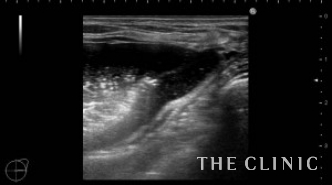

この方は2ヵ月前にヒアルロン酸注入を受けられていますが、除去したいとのご希望でご来院されました。エコーにて、乳腺下に一塊のものと蜂の巣状、皮下にも蜂の巣状のヒアルロン酸のしこりを確認しました。

左)吸引後、しこりは消失しました。

右)除去したヒアルロン酸です。